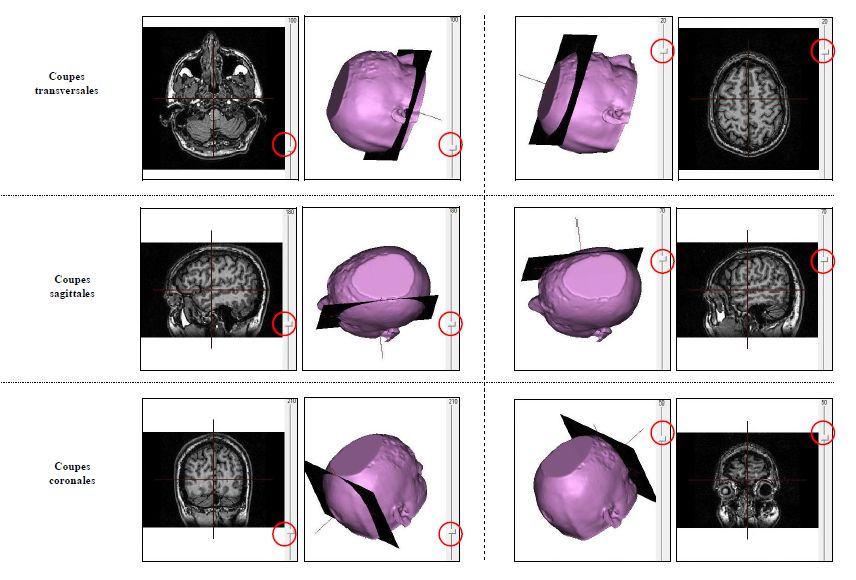

Eduanatomist

Fiche technq 2

Ancien logiciel : EduAnatomist et Neuropeda

Informations sur les images AnaPeda